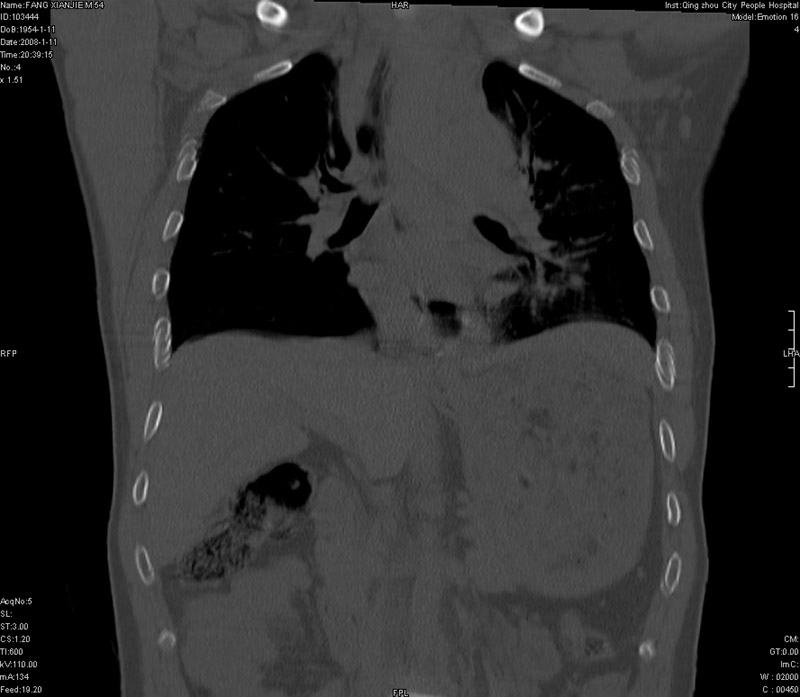

男性,40岁。胸部被车压伤伴胸痛1小时来院就诊。检查:一般情况尚可,血压110/80,胸部及上腹部压痛。结果在三天后公布。骨窗在横断位、冠矢状显示肋骨、胸椎、和胸骨未见骨折征象。

ct11308:胸部外伤1小时(证实病例) (2008-1-13 16:2)结果如下:病人入院后两小时后症状加重,8小时后在征得病人家属同意做了ct增强扫描。如下图。最终临床诊断:外伤性胸主动脉破裂并纵隔内血肿。由于有运动性伪影,胸骨在矢状面重建的图像似有骨折征,这是一种假象,我们称之为“假骨折”,这在多层ct重建中经常性遇到,必要时要结合横断图像鉴别之。现在,病人的一般情况较差,是否要手术家属尚有争议,如果手术修补,难度较大,需要专门预定制作固定支架。

以下是引用拾荒者在2008-1-16 18:46:00的发言:[br]ct11308:胸部外伤1小时(证实病例) (2008-1-13 16:2)结果如下:病人入院后两小时后症状加重,8小时后在征得病人家属同意做了ct增强扫描。如下图。最终临床诊断:外伤性胸主动脉破裂并纵隔内血肿。由于有运动性伪影,胸骨在矢状面重建的图像似有骨折征,这是一种假象,我们称之为“假骨折”,还有双侧肋骨的“假骨折”,这在多层ct重建中经常性遇到,必要时要结合横断图像鉴别之。现在,病人的一般情况较差,是否要手术家属尚有争议,如果手术修补,难度较大,需要专门预定制作固定支架。[br][br]再次表示感谢!

当然,对于该病例,其它非重要的诊断还有:右侧少量气胸;左侧胸腔积液;左侧轻度肺挫裂伤。对于纵隔内血肿,我们曾经遇到过多例,也有怀疑主动脉的破裂,但是,均未得到具体出血部位的明确诊断。